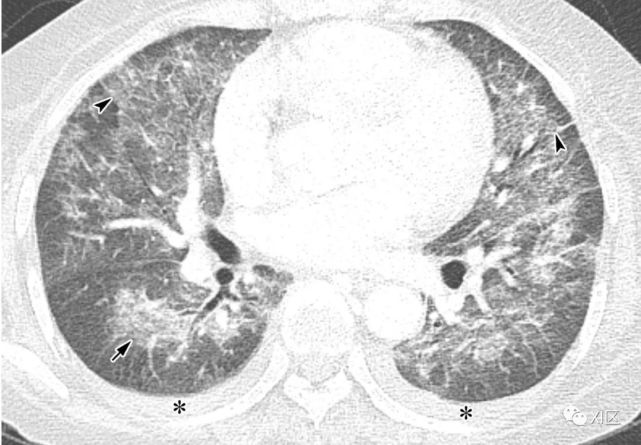

图13 63岁的男子,原发性中枢神经系统淋巴瘤化疗后合并发热,诊断为人博卡病毒肺炎

(上)胸部X线片显示两肺均弥漫性不规则斑块状实变(箭)和GGO。在同一天获得的轴位薄层(1mm)胸部CT图像显示,沿着支气管血管束和肺部周边区域出现不规则的斑块状实变(箭),支气管壁增厚,小叶间隔增厚 (箭头),伴有少量双侧胸腔积液(*)。

Koo H J , Lim S , Choe J , et al. Radiographic and CT Features of Viral Pneumonia[J]. Radiographics, 2018, 38(3):719-739.